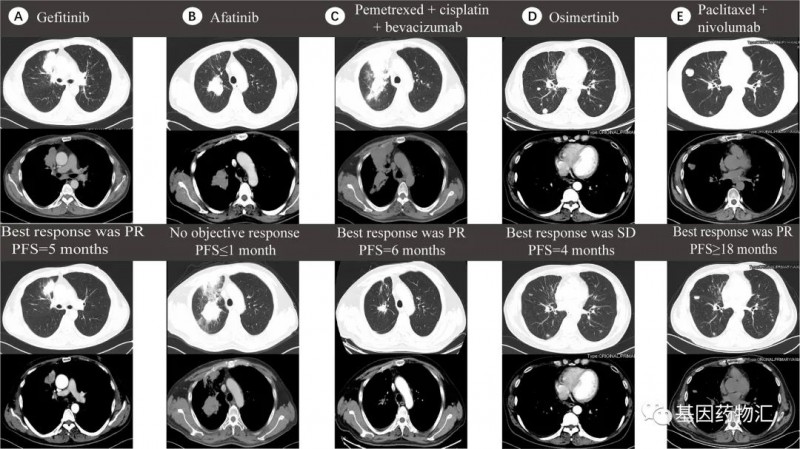

在另一个案例当中,患者同样是肺腺癌,从最初EGFR ex19del突变使用吉非替尼,到耐药后出现EGFR T790M突变是使用奥希替尼,最终因KRAS外显子3(R68S)突变阳性而耐药。患者后续的治疗选择了白蛋白紫杉醇+纳武单抗(纳武利尤单抗),4个周期的治疗后,达到了临床部分缓解!